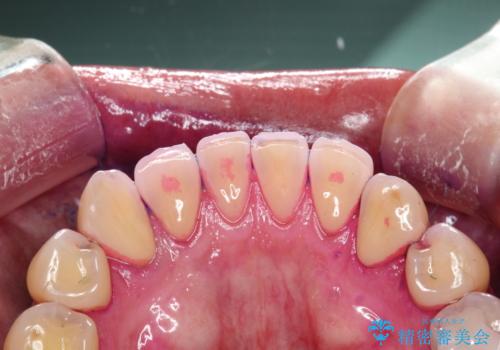

- 半年ぶりの来院できれいにクリーニンングしてほしいとのことでした。染め出しをして歯磨きチェックとPMTC30分コースを行いました。

歯の染め出しとは、汚れがついている部分に色が着いて、どの部分が磨けていないか分かりやすく確認することができます。歯の表面についているプラークは歯と同じ色をしているので見た目では分かりにくいものです。そのため、染め出しをすると、長い期間付着している汚れが濃い色になったり、どの部分が苦手で磨き残してしまっているか確認することが出来ます。